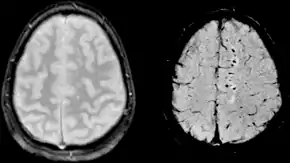

Gradient recalled echo (GRE) imaging is the conventional way to detect hemorrhage in CAA, however SWI is a much more sensitive technique that can reveal many micro-hemorrhages that are missed on GRE images.[7] A conventional gradient echo T2*-weighted image (left, TE=20 ms) shows some low-signal foci associated with CAA. On the other hand, an SWI image (center, with a resolution of 0.5 mm x 0.5 mm x 2.0 mm, projected over 8mm) shows many more associated low-signal foci. Phase images were used to enhance the effect of the local hemosiderin build-up. An example phase image (right) with yet higher resolution of 0.25 mm x 0.25 mm x 2.0 mm shows a clear ability to localize multiple CAA-associated foci.